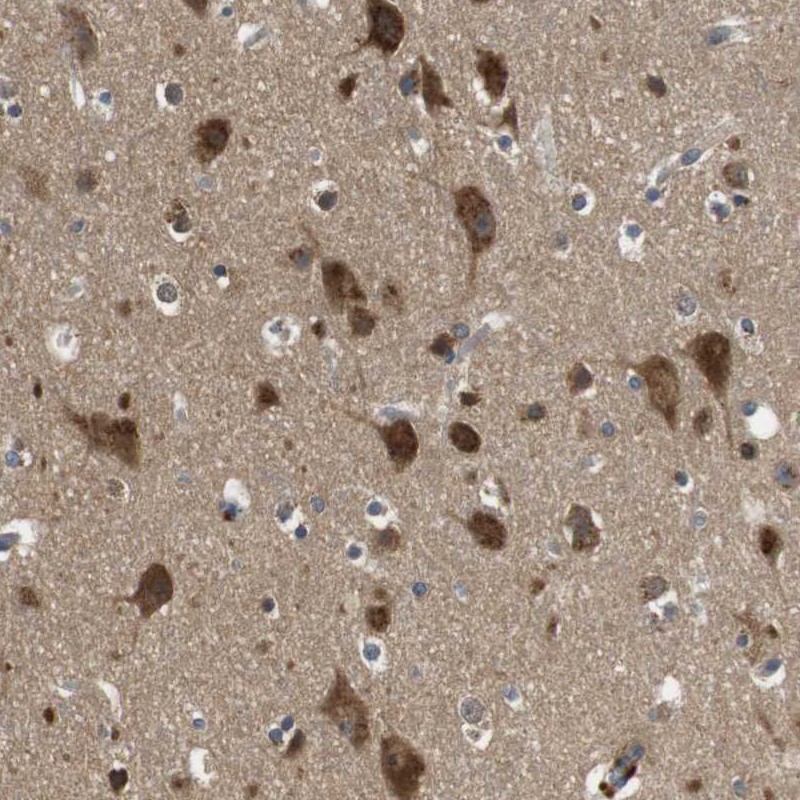

Immunohistochemical staining of human cerebral cortex shows strong cytoplasmic positivity in neuronal cells.